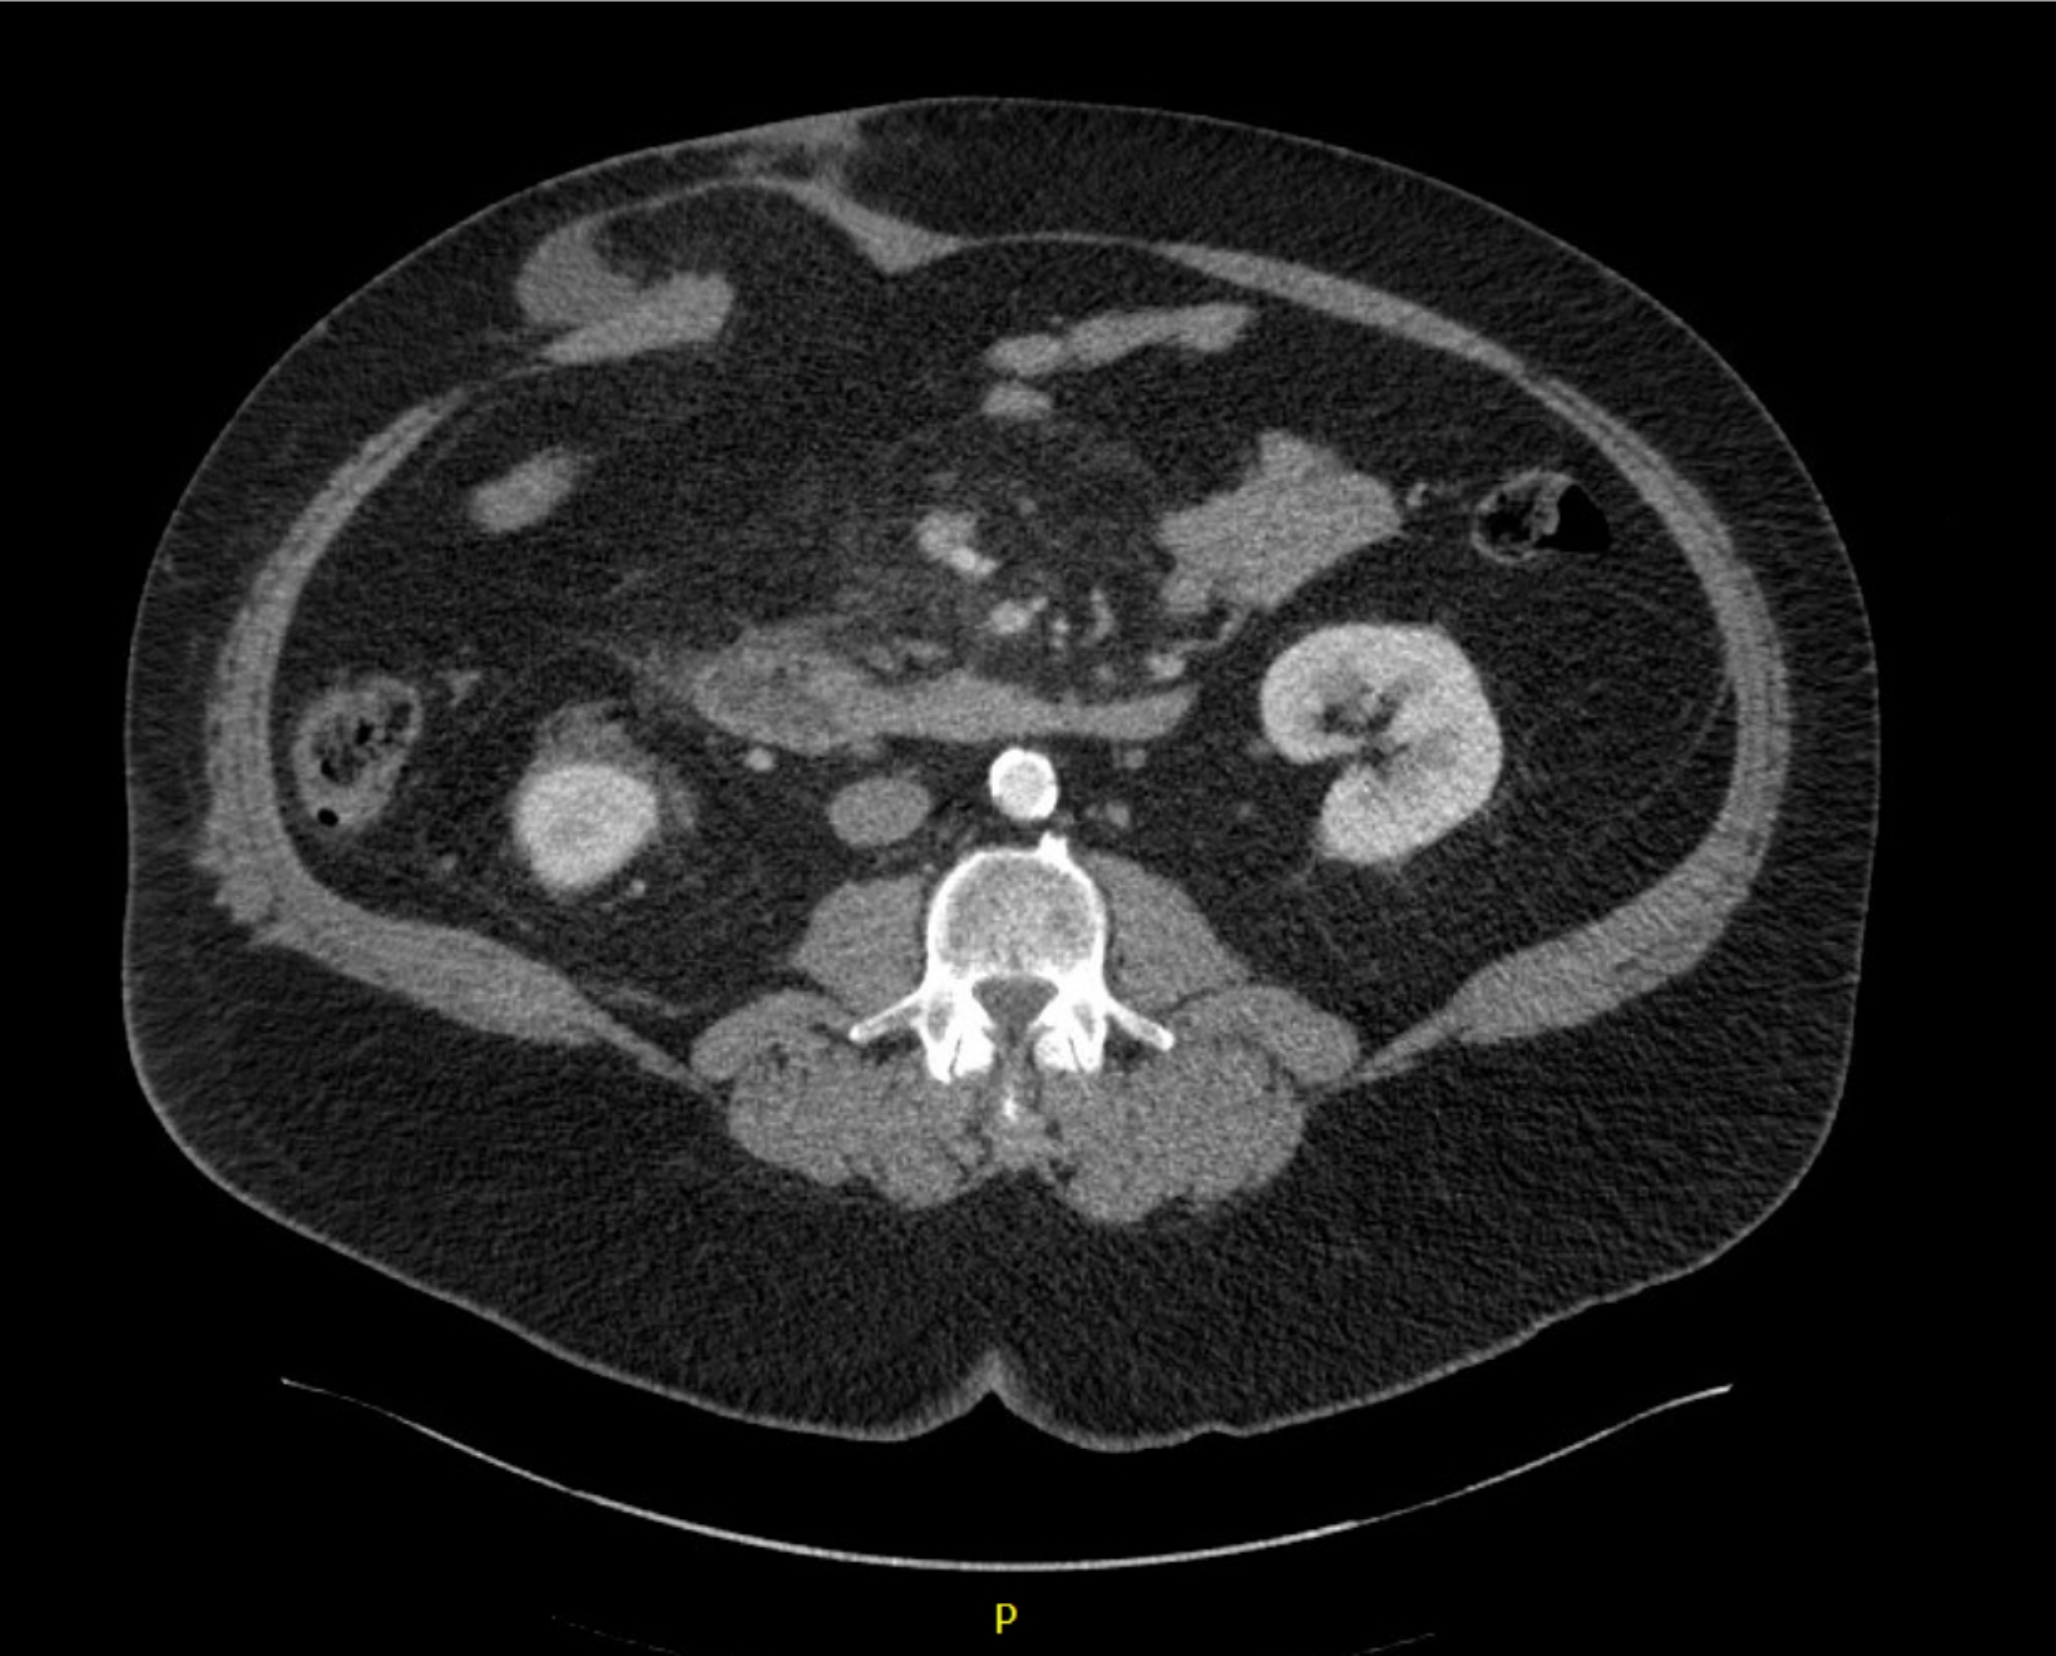

Radiographic images were individually reviewed by members of the colorectal and abdominal wall reconstruction teams (LB, MMS, NM, AK, SJ, KB, BM, DK, AP, SRS, MR, SDH, and CP) for presence of ISIH. The definition of ISIH was “Any abdominal wall gap with or without [a] bulge in the area of a postoperative scar perceptible or palpable by clinical examination or imaging” (as described by Korenkov et al.) for which our surgeons felt they would offer surgical repair [17]. (Fig. 1)

Fig. 1

Ileostomy Site Incisional Hernia